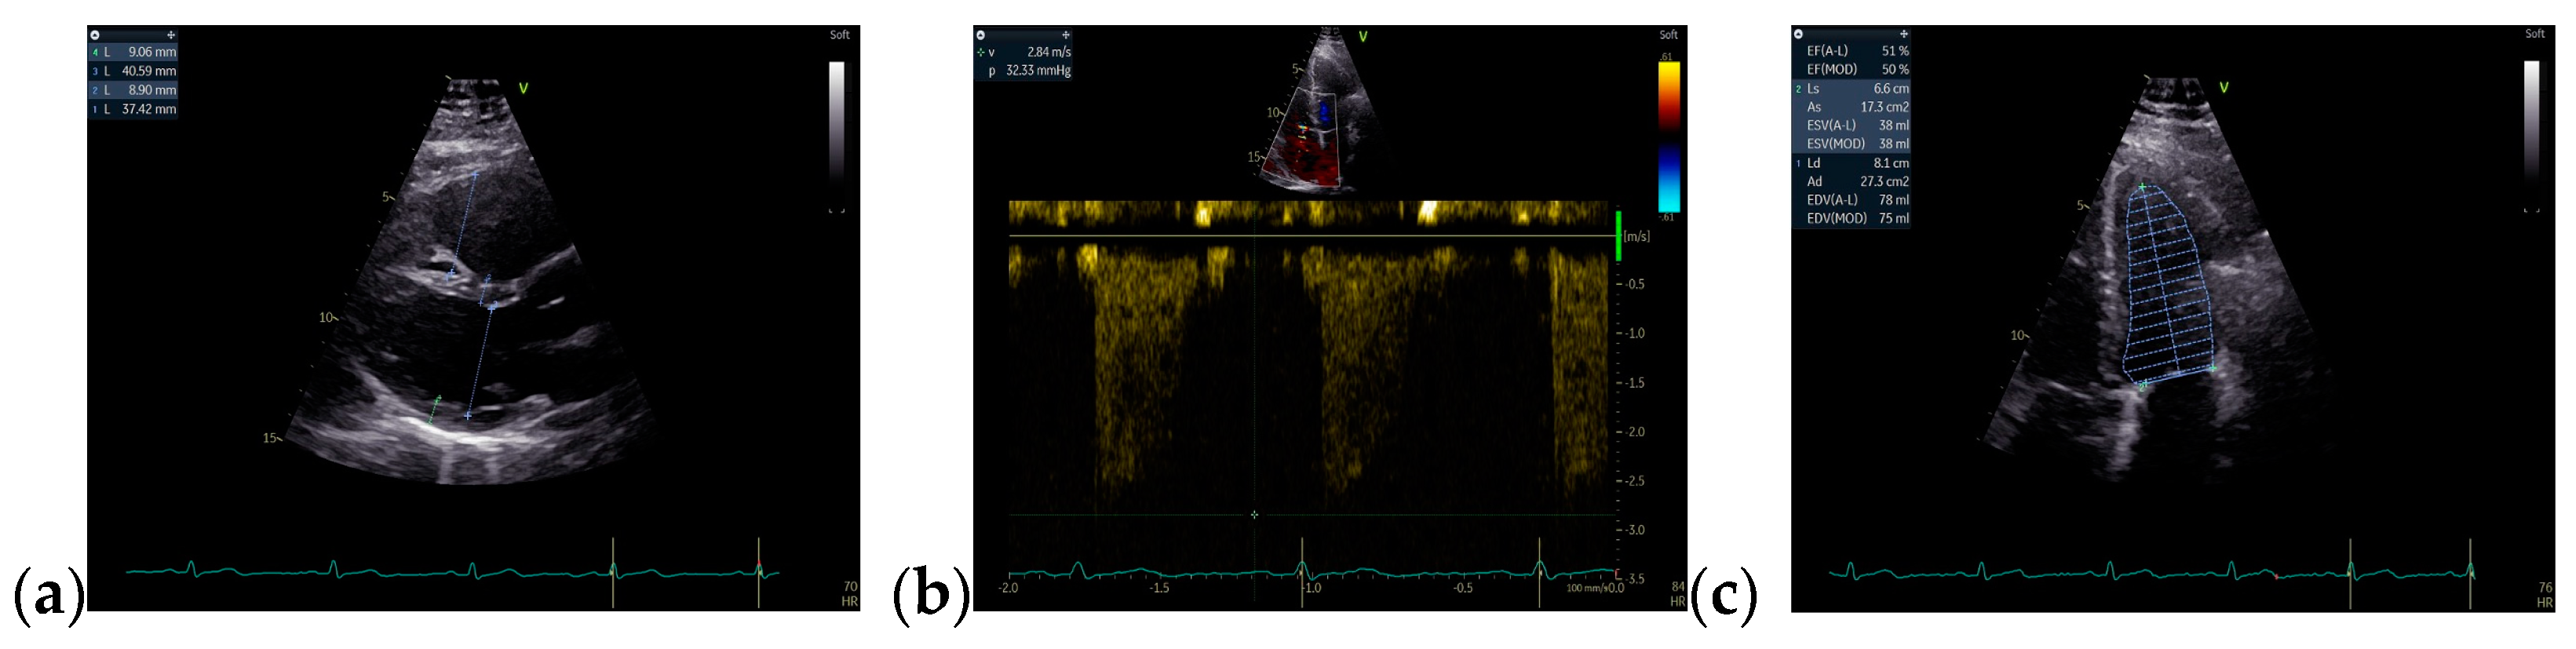

On admission, a TTE was performed and confirmed Ebstein’s anomaly. The main findings of the TTE were non-dilated left ventricle with an ejection fraction of 50% evaluated using Simpson’s method, dilated right chambers, atrialization of the RV, apical insertion of the septal cusp of the tricuspid valve, and mild functional tricuspid regurgitation (Figure 8).

Figure 8.

TTE on admission: (a) Apical 4-chamber view: dilated right cavities with a RV diameter of 7, 3 cm; (b) Apical 4-chamber view: total volume of the RV—252 mL; (c) Apical 4-chamber view: functional RV volume—170 mL; (d) Apical 4-chamber view: atrialized RV volume—123 mL; Abbreviations: TTE—transthoracic echocardiography; RV—right ventricle.